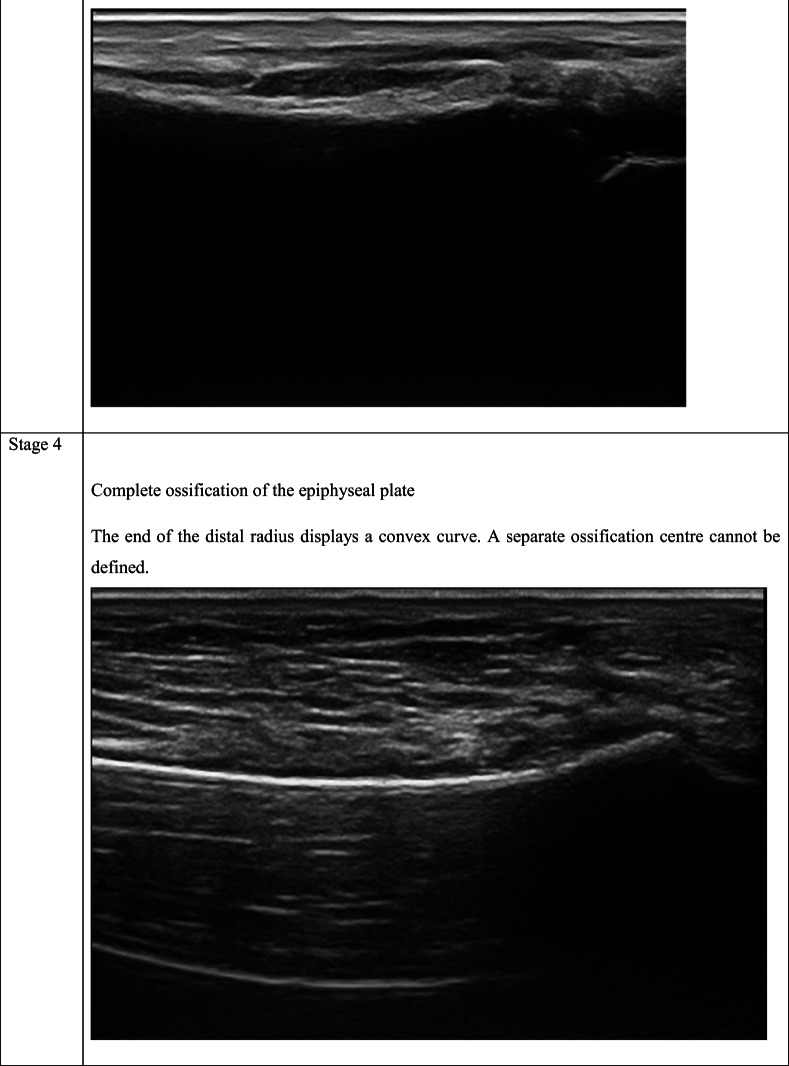

As shown in Table 2, the staging system described by Schulz et al. [27] for the clavicle, modified by Schmidt et al. [25] for the distal radius, was used.

Overlap is among the reported limitations of the USG method [2, 29]. Anatomical features that differ with age may prevent the evaluation of ossification depending on the area studied [2, 29]. Forensic age estimation for the wrist as well as clinically based studies are available, and it is known that the distal radial epiphysis is well defined on USG images [21, 22, 37]. According to the experience obtained in this study, the echogenic view of the secondary ossification center and the acoustic shadow formed are also observed along the bone surface of distal radius. When ossification between the distal of radius and the secondary ossification center has not occurred, there is no continuity on the bone surface. For this reason, the acoustic shadow does not appear in stage 2. When the integrity and consequently continuity of the bone cortex occurs in the areas with ossification, the acoustic shadow is continuously observed in these parts in stage 4. In addition, due to centrifugal ossification, there are areas where the continuity of the bone surface is formed and not yet formed. Therefore, it is seen that there is or does not have acoustic shadow in these areas. This imaging feature helps to discriminate stage 3 from stage 2 and 4. Ultrasonography offers the opportunity to evaluate different planes simultaneously during the examination. At the same time, it provides the opportunity to re-evaluate without time limitation areas where it is suspected to be reproducible. In addition to constituting a real-time review, the entire examination can be recorded in video format, allowing for later evaluation, owing to today’s developing PACS (picture archiving and communication system) capabilities. The images obtained within the scope of a standardized examination allow later evaluation by other experts on the subject.